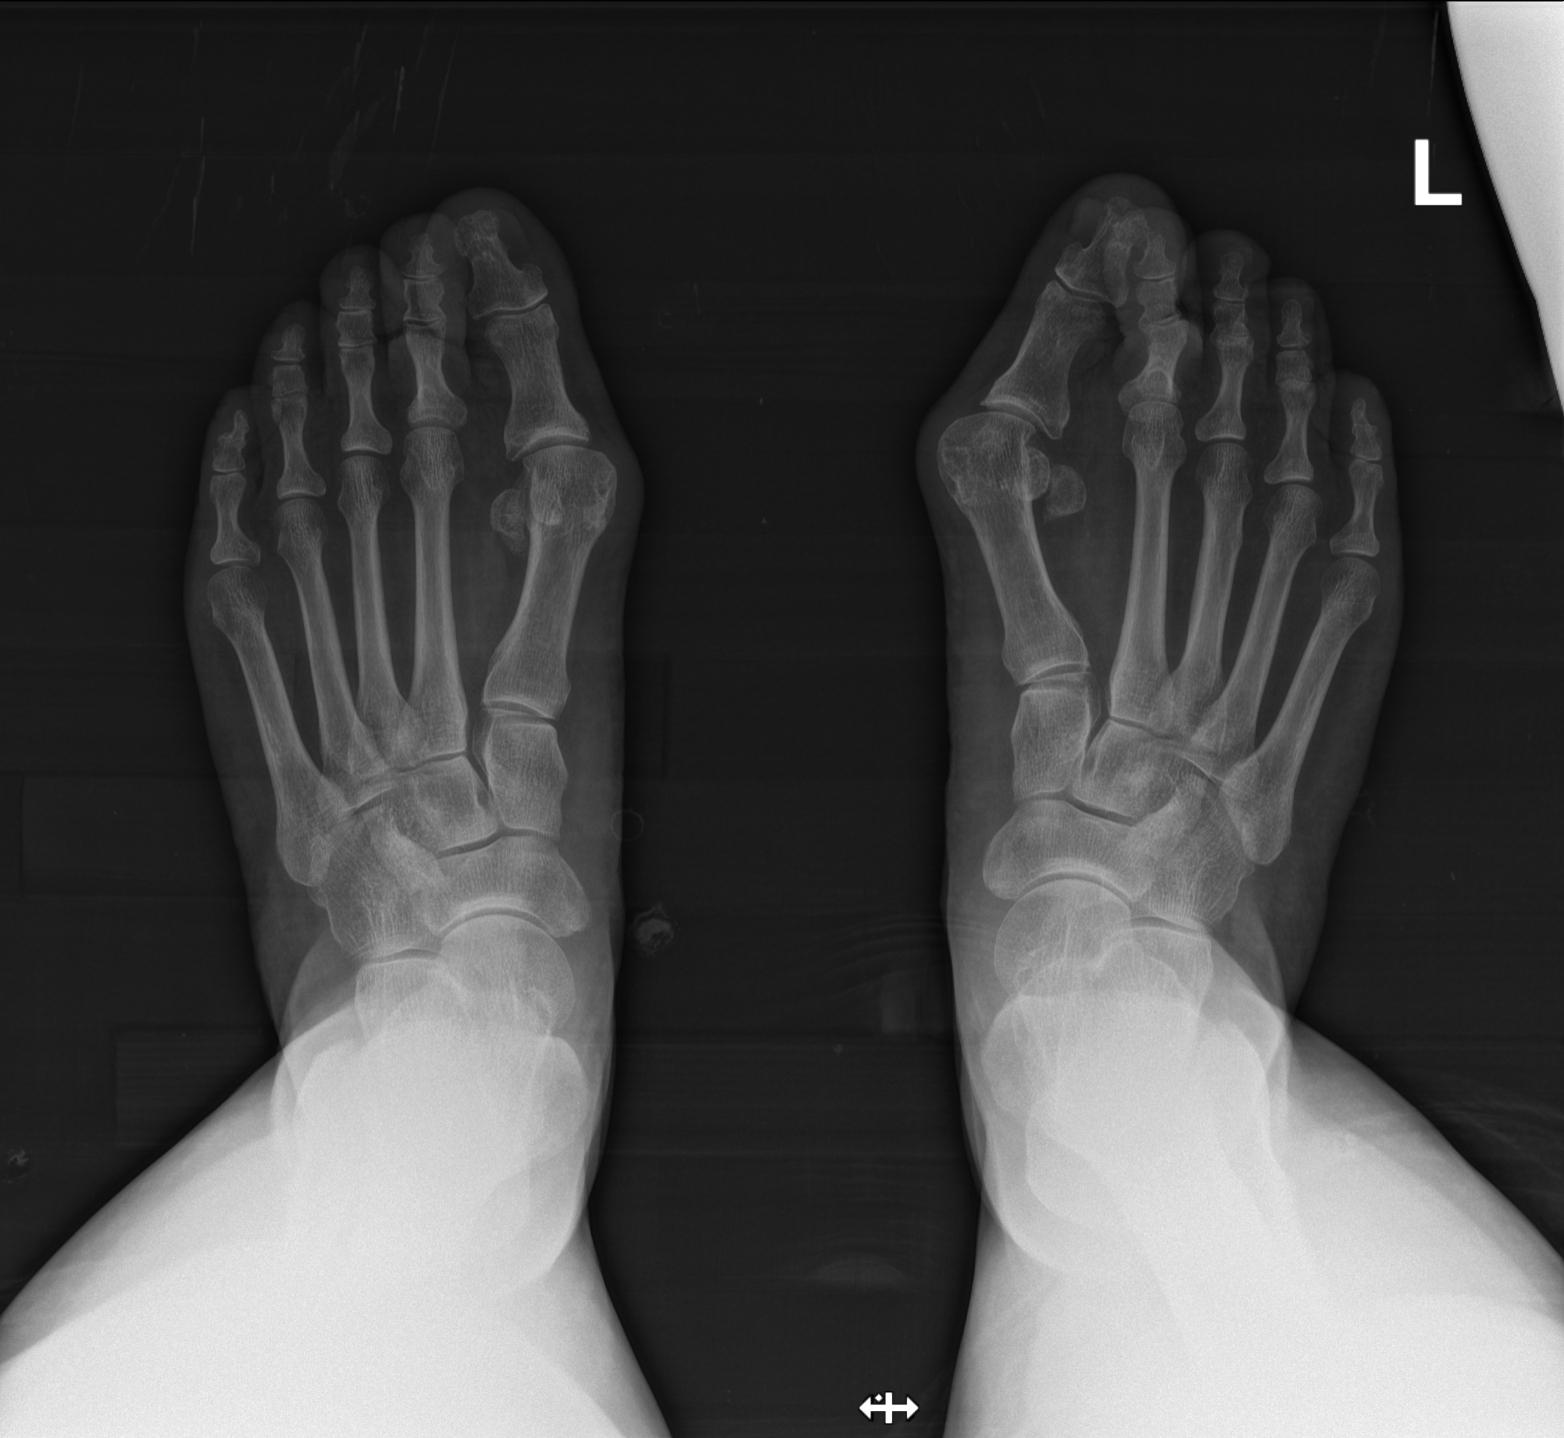

术前影像

术前